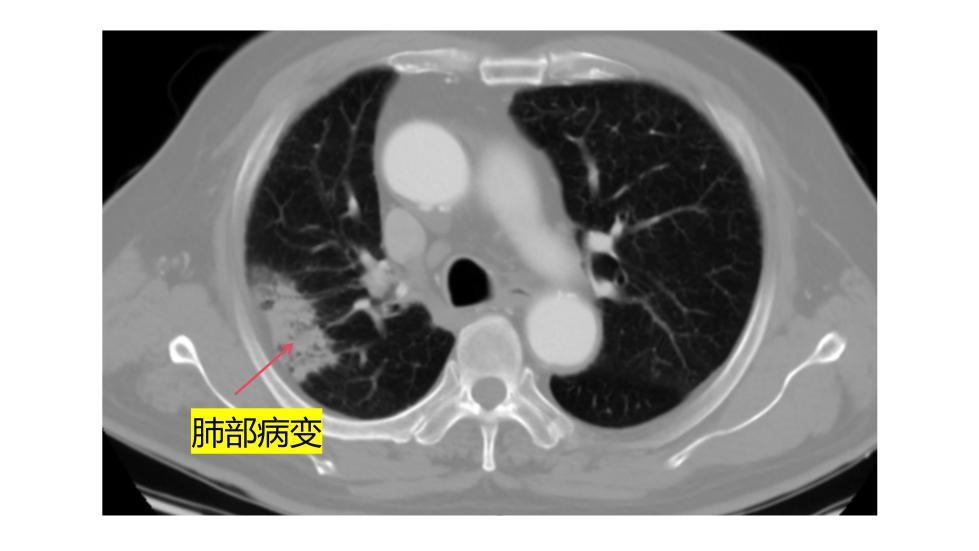

据了解,王大爷的病情发现于2025年底的一次肺部CT检查。检查显示,他的主动脉弓部长了一个累及颈动脉的动脉瘤,随时可能破裂致命。然而,传统的开胸手术需要让心脏停跳、体温降到很低、创伤极大,对心肺功能要求很高。“老人已经78岁了,肺功能又不好,根本耐受不了这种常规开胸大手术。”医院血管外科中心舒畅教授解释。传统手术“走不通”,舒畅教授团队决定,采用CS 一体式弓部三分支重建系统,为老人制定新的治疗方案。